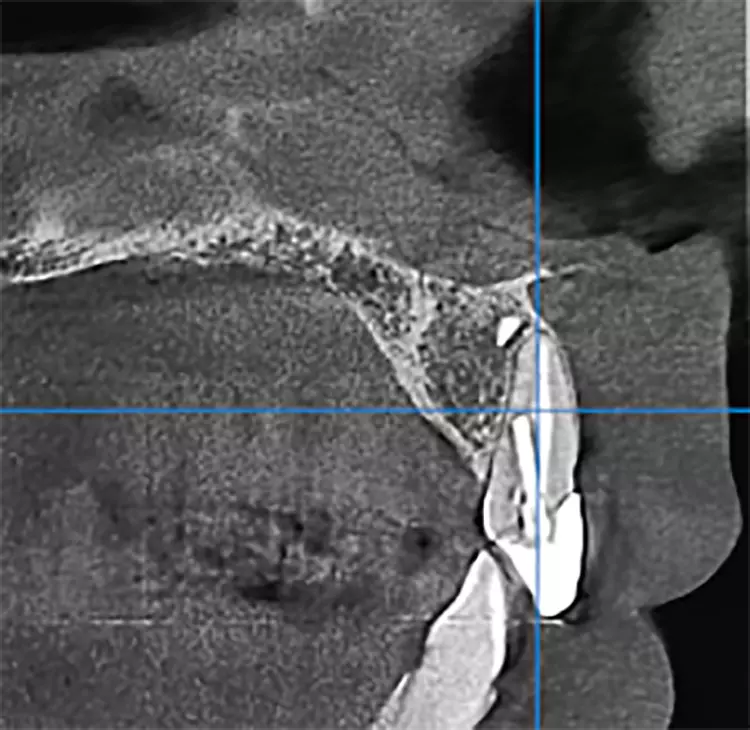

Bei diesem 49-jährigen, allgemeinanamnestisch unauffälligen Patienten liegen diverse ästhetisch störende Zahnstellungsanomalien vor, wobei Zahn 21 bei extremer Elongation frakturierte (Abb. 2a). Nach einer Übergangsversorgung mittels provisorischer Stiftkrone (Abb. 2b) entschied sich der Patient für eine Zahnentfernung bei gleichzeitiger Implantation. Im Ausgangs-DVT (Abb. 2c und d) zeigt sich im Cross-Sectional, wie weit der Processus alveolaris zurückliegt.

Im präoperativ angefertigten DVT (Abb. 3b und c) zeigte sich um die Wurzelspitze ein chronisches Entzündungsgeschehen, welches die vestibuläre Lamelle im apikalen Wurzelbereich des Zahnes 23 komplett aufgelöst hat. Da jedoch der Bereich direkt apikal von 23 nicht vom Geschehen betroffen war, fiel die Entscheidung zur Sofortimplantation auch, da der Patient blutverdünnende Medikamente einnehmen musste, welche durch Kombination von Extraktion und Implantation nur einmal abgesetzt werden mussten. In diesem Fall war aufgrund des Knochendefektes die Bildung eines Volllappens mit Entlastung unumgänglich.